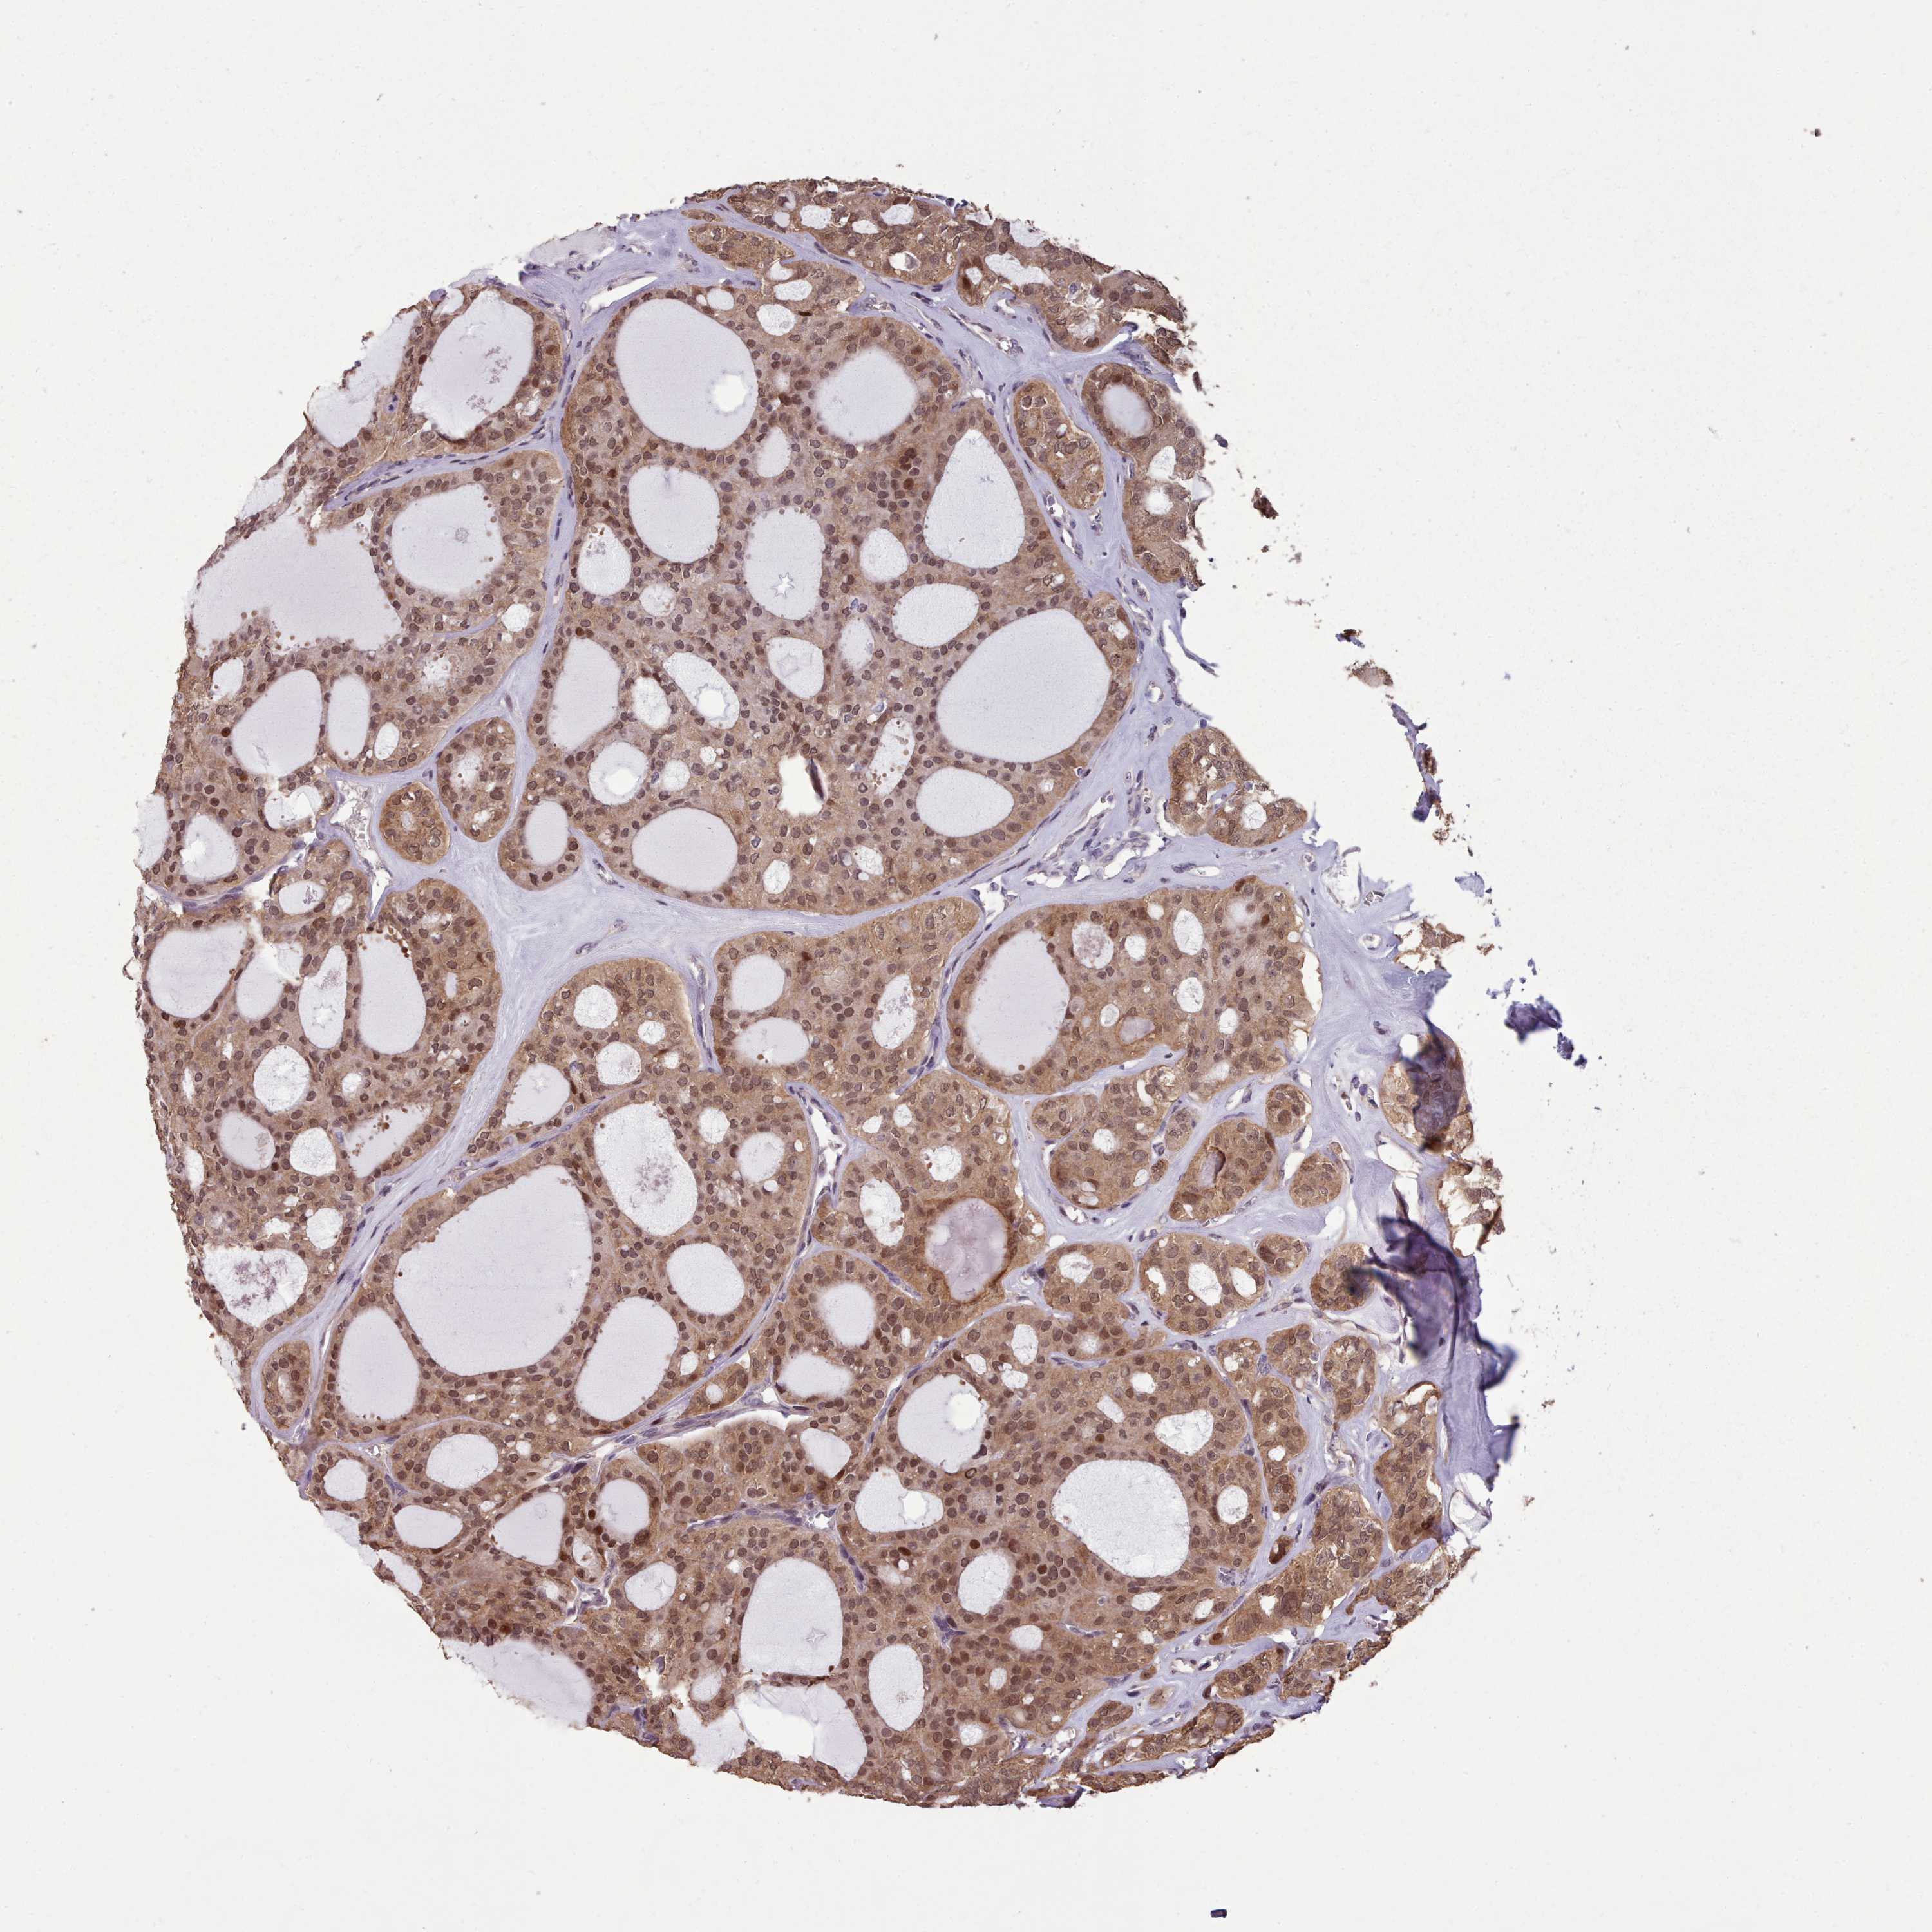

THYROID CANCER - Protein expressioni

A mouse-over function shows sample information and annotation data. Click on an image to view it in a full screen mode. Samples can be filtered based on level of antibody staining by selecting one or several of the following categories: high, medium, low and not detected. The assay and annotation is described here.

Note that samples used for immunohistochemistry by the Human Protein Atlas do not correspond to samples in the TCGA dataset.

Antibody stainingi

Antibody staining in the annotated cell types in the current human tissue is reported as not detected, low, medium, or high, based on conventional immunohistochemistry profiling in selected tissues. This score is based on the combination of the staining intensity and fraction of stained cells.

Each image is clickable and will lead to virtual microscopy that enables deeper exploration of all samples and also displays staining intensity scores, fraction scores and subcellular localization as well as patient and tissue information for each sample.

Antibody HPA051294

Staining

High

Medium

Low

Not detected

Intensity

Strong

Moderate

Weak

Negative

Quantity

>75%

75%-25%

<25%

None

Location

Nuclear

Cytoplasmic/membranous

Cytoplasmic/membranous,nuclear

Papillary adenocarcinoma, NOS

Follicular adenoma carcinoma, NOS